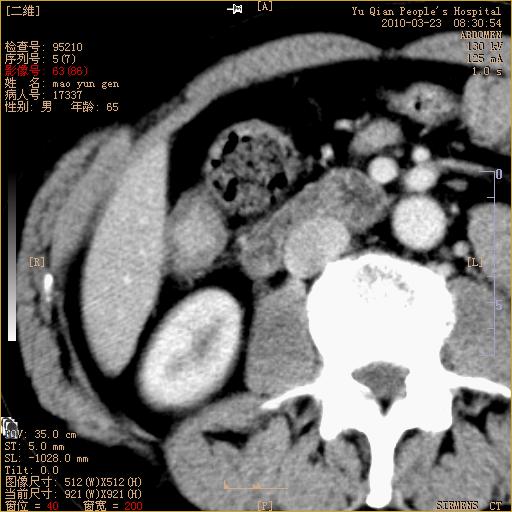

标题: CT25266:消瘦月余,前来肝部检查,请看看肠腔 [打印本页]

标题: CT25266:消瘦月余,前来肝部检查,请看看肠腔

升结肠肠壁增厚,不均强化,考虑升结肠腺癌可能性,建议肠镜检查。

1)考虑升结肠癌。2)右肾小囊肿。